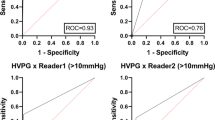

Splenic ECV revealed a perfect diagnostic performance with an area under the curve (AUC) of 1.000, a sensitivity of 100%, and a specificity of 100% (see Fig. 2, Fig. 3, and Table 4). There were no significant differences in the diagnostic performance of splenic and hepatic ECV (AUC, 1.000 vs. 0.954; p = 0.116). The diagnostic performance of splenic ECV was also not significantly higher compared with that of hepatic native T1 (AUC, 1.000 vs. 0.926; p = 0.105) but significantly higher than that of splenic native T1 (AUC, 1.000 vs. 0.806; p = 0.005). There were no significant differences in the diagnostic performance of native splenic and hepatic T1 (AUC, 0.806 vs. 0.926, p = 0.058). Hepatic ECV showed a higher diagnostic performance compared with native splenic T1 (AUC, 0.954 vs. 0.806, p = 0.038). Between hepatic ECV and hepatic native T1, no significant differences in diagnostic performance were observed. The diagnostic performance of hepatic and splenic T2 was significantly lower than that of the splenic and hepatic native T1 and ECV parameters.

Graphs show receiver operating characteristic curves for diagnosis of clinically significant portal hypertension (direct hepatic venous pressure gradient, ≥ 10 mmHg) in the derivation cohort. Curves are given for hepatic T1 relaxation times (area under curve [AUC], 0.926), hepatic ECV (AUC, 0.954), hepatic T2 relaxation times (AUC, 0.731), splenic T1 relaxation times (AUC, 0.806), splenic T2 relaxation times (AUC, 0.736), and splenic ECV (AUC, 1.000)

Validation cohort

The parameters of the diagnostic performance of the validation cohort are given in Table 4. The 95% confidence intervals of diagnostic performance were comparable between the derivation and the validation cohort.

Unlike ECV, native hepatic T1 (AUC 0.926) performed better than native splenic T1 (AUC 0.806) in the derivation cohort. This might be explained by a higher contribution of fibrosis to changes in T1 values, as fibrotic changes are more remarkable in hepatic than in splenic parenchyma. Splenic and hepatic T2 mapping parameters had a similar diagnostic performance to patients diagnosed with clinically significant portal hypertension with AUCs of 0.736 and 0.731, respectively. According to previous cardiac studies, increased T2 relaxation times are mainly driven due to myocardial edema or inflammation [27]. Therefore, increased T2 relaxation times in abdominal mapping probably reflect the coexistence of inflammatory or edematous changes in regions of fibrosis [28, 29], which does not correlate well with measures of portal hypertension.